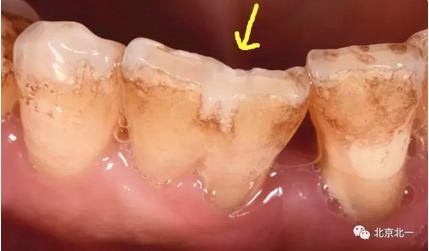

圖九:2016年10月18日復(fù)查時照片。

處理:予以重新清潔,重新粘接固位。并進(jìn)行衛(wèi)生宣教,以及牙周基礎(chǔ)治療。

附:關(guān)注箭頭所示,診斷為結(jié)合牙還是融合牙?牙冠結(jié)合一起, 牙根分開。